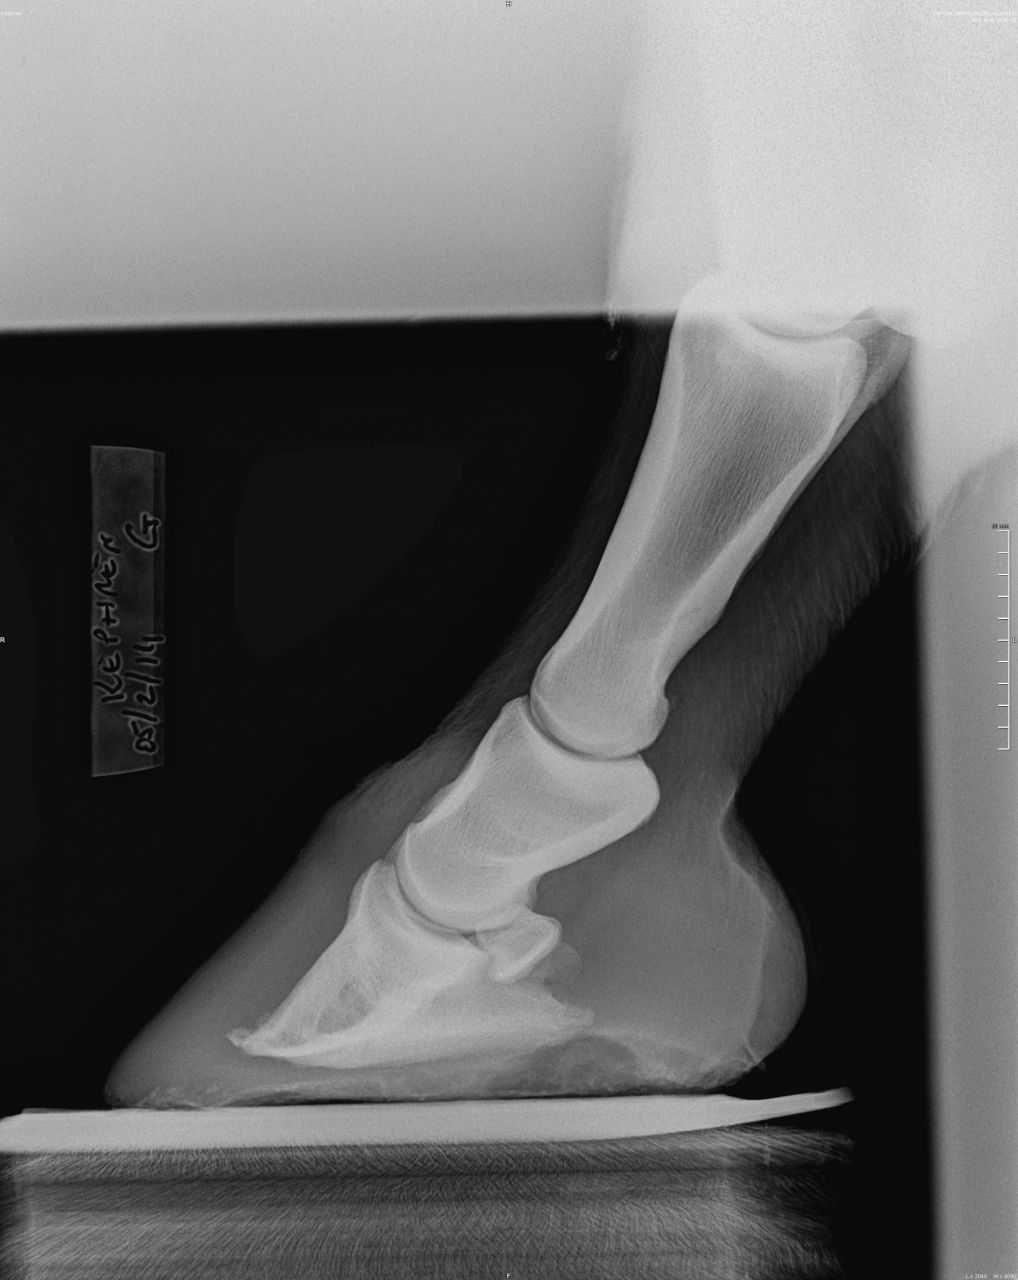

DéconnectéDire merci | Sur la radio de 2011, on voit déjà que le bord solaire de P3 est irrégulier, voir possiblement fracturé sur le côté droit. Je ne vois pas de bascule plus que cela de P3. Dommage qu'il n'y ait pas de nouvelle vue récente du bord solaire. Sur les deux autres radiographies récente, on voit un remaniement osseux de la pinte de P3 et ce qui pourrait être une plus forte perte osseuse du bord solaire que sur les radios de 2011 – mais il faudrait une vue "bord solaire" récente pour confirmer ou infirmer. Mais surtout, ce qui me saute aux yeux sur la radios récentes, c'est 1/ P2 parallèle au sol (ce qui contribue à endommager encore plus P3 2/ le mauvais alignement des phalanges (alors qu'il était quasi correct en 2011), avec un axe pied-pâturon brisé vers l'arrière. |

DéconnectéDire merci | En premier lieu, et avec mes excuses, c'est P3 parallèle au sol que je voulais écrire. Oui, les phalanges étaient mieux alignées en 2011. Peut-être que le cheval marche mieux et que son sabot ressemble à quelque chose (photo ?), mais une chose est indéniable, P3 s'est détériorée depuis 2011. |

DéconnectéDire merci | 2011 [url=https://www.1cheval.com/membre/services/photos/images/176072.jpg] ![]() [/url] 2014 [url=https://www.1cheval.com/membre/services/photos/images/176073.jpg] ![]() [/url] Message édité le 10/02/14 à 12:10 |

| Dire merci | pour moi ce qui a visiblement changé entre les deux clichés de profil c'est le paturon qui s'est verticalisé. Il appuie donc plus sur l'avant du pied. Peut être une douleur ou gène à l'arrière ? Je me pose vraiment la question parce que le mien qui n'a malheureusement en ce moment pas les fourchettes en bon état et devrait donc avoir mal à l'arrière du pied lui ne pèse pas devant. |

DéconnectéDire merci | Sur les radios de 2011, il n'y a pas de bascule de P3. Juste une pince fuyante, et encore, seulement sur la moitié basse de la paroi. Il est su et connu que maintenir P3 parallèle au sol, en ratiboisant les talons, engendre à moyen terme une détérioration du bord solaire de P3. En plus de désaxer les phalanges. C'est relativement simple à comprendre : lorsque P3 est parallèle au sol, les cartilages ungulaires n'ont plus de rôle à jouer, donc ils ne peuvent plus amortir en se distordant, et on se retrouve, du point de vue de P3, dans un cas similaire à celui d'une voiture qui "talonne", c'est-à-dire que c'est la structure osseuses qui encaisse directement les forces de réaction du sol. Quand on fait en sorte que P3 fasse un angle de 5-6° avec le sol, comme c'est communément admis que cela doit être (et comme l'a confirmée l'étude menée en Australie sur les Brumbies), l'arche constituée par P3+cartilage a une capacité de se déformer (de s'écraser) du fait des qualités mécaniques des cartilages ungulaires (qui peuvent se déformer et cherchent toujours à reprendre leur forme originelle – s'il n'y a pas maladie genre fourbure). Morale de tout ceci : maintenir volontairement P3 parallèle au sol dans la durée engendre des dégâts à P3 (et aussi, par répercussions, des troubles ostéopathiques "plus haut" . |